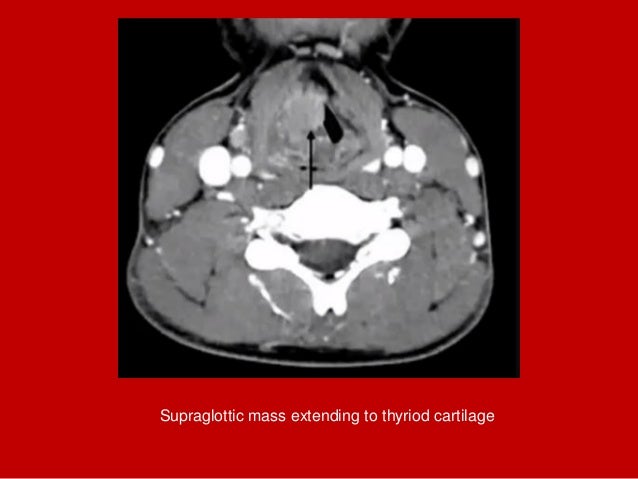

19. 19. Supraglottic mass extending to thyriod cartilage